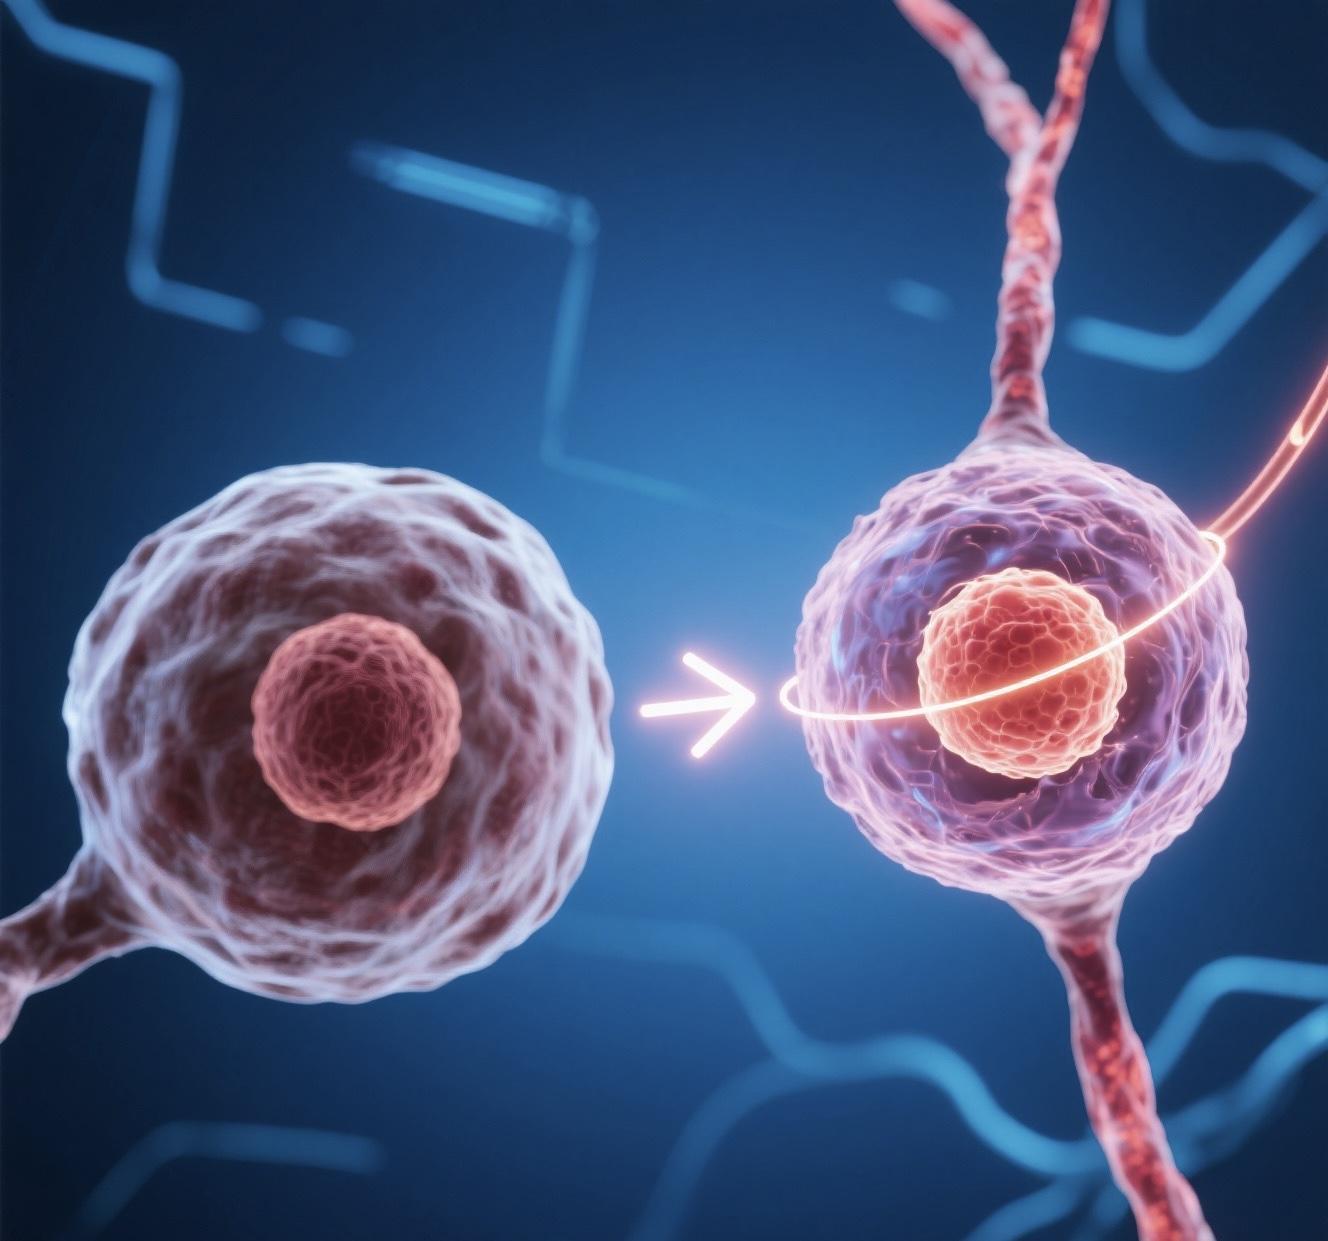

“基因魔剪”攜手AI提升DNA編輯精度